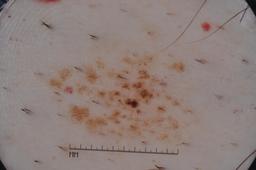

MSK-4

- Name: MSK-4

Description:

Images found based on a search for patients with a personal history, clinical diagnosis, or differential diagnosis of melanoma. All diagnoses confirmed by histopathology.